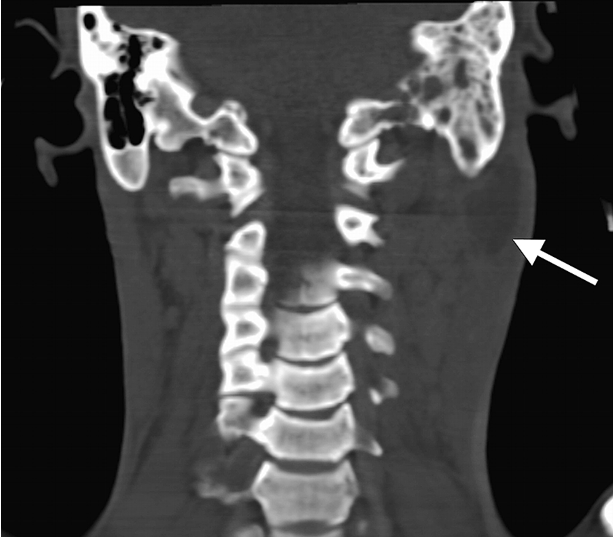

Extracranial Complications

- Extension of infection to the neck

- Bezold abscess (extension of infection from mastoid to SCM)